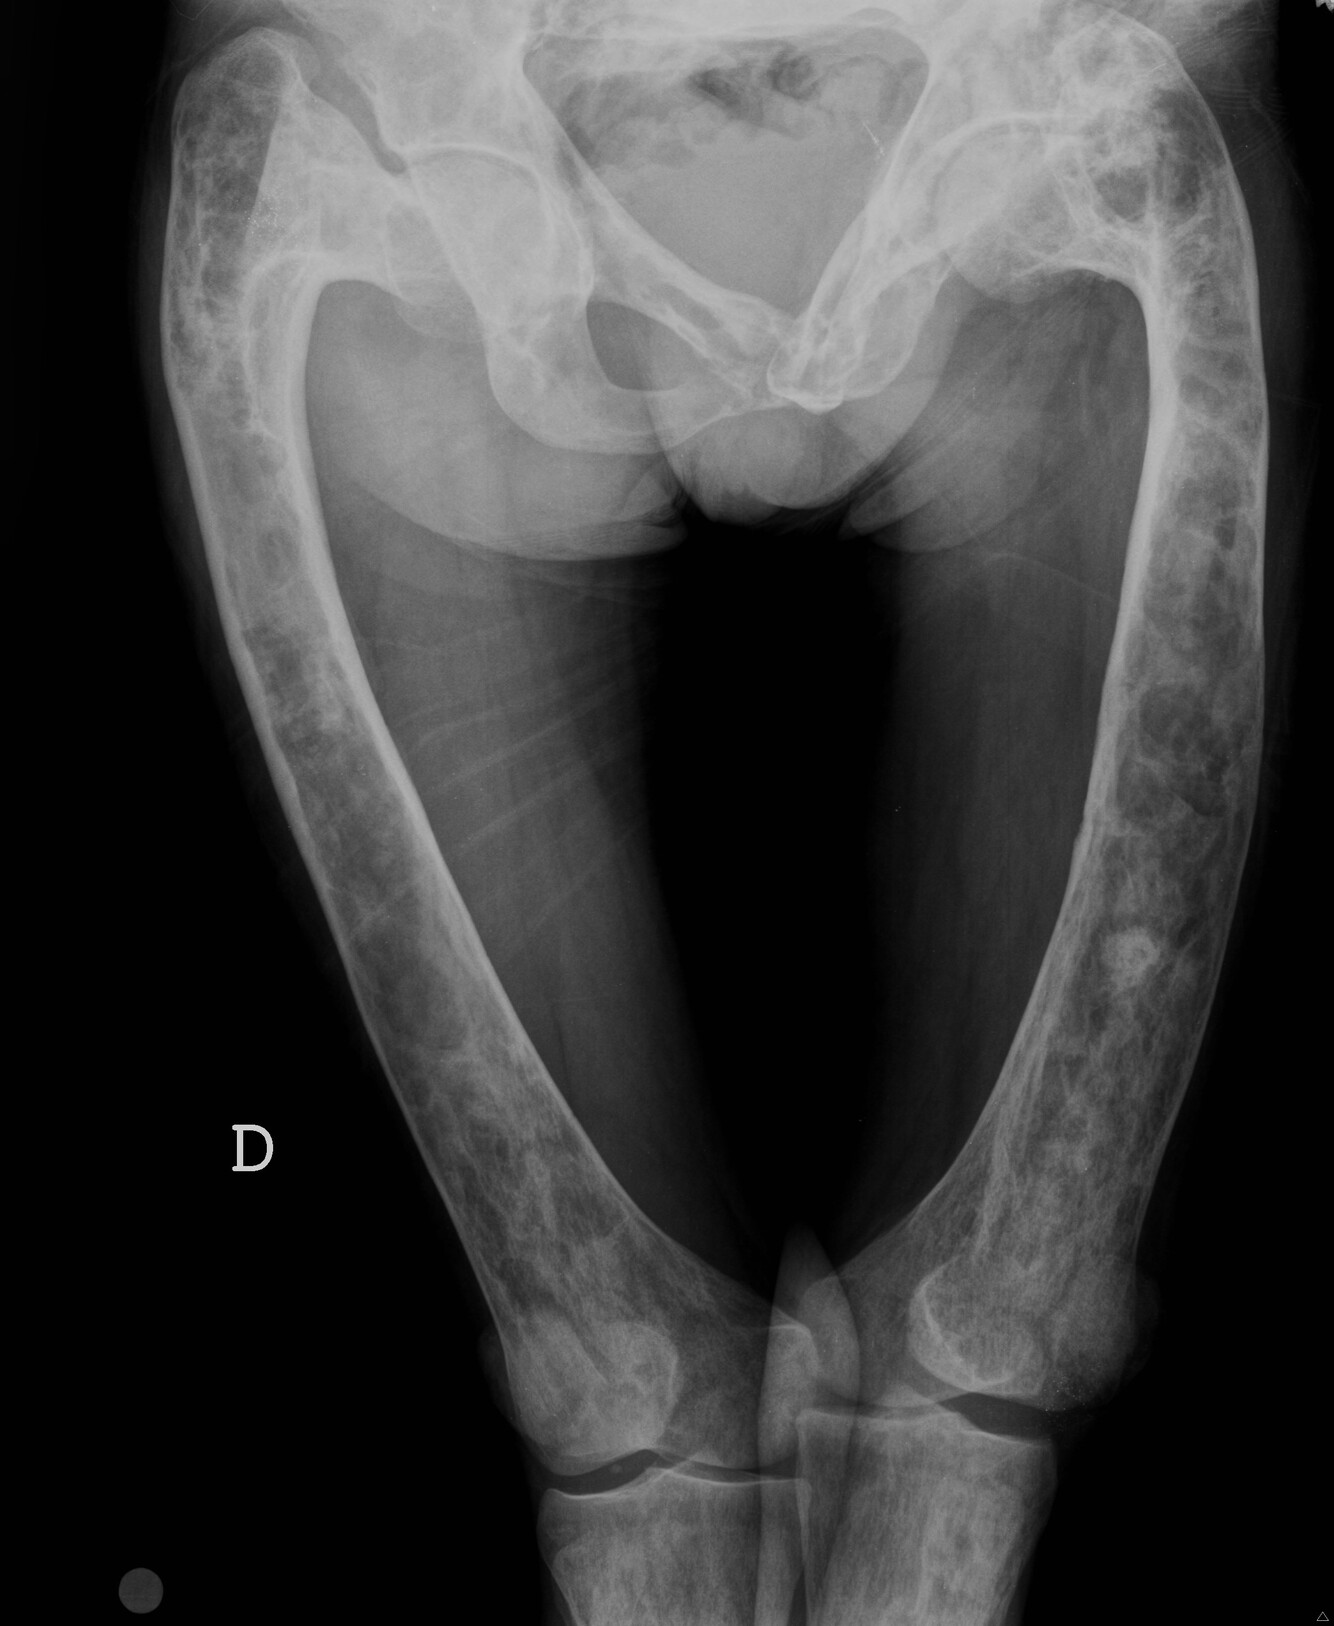

What is the epidemiology of a chondrosarcoma?

Malignant cartilage producing tumour Usually >40

What is the site preference of chondrosarcomas?

Axial skeleton Femur/tibia/ pelvis

What are X-ray findings of chondrosarcomas?

Lytic lesion with fluffy calcification